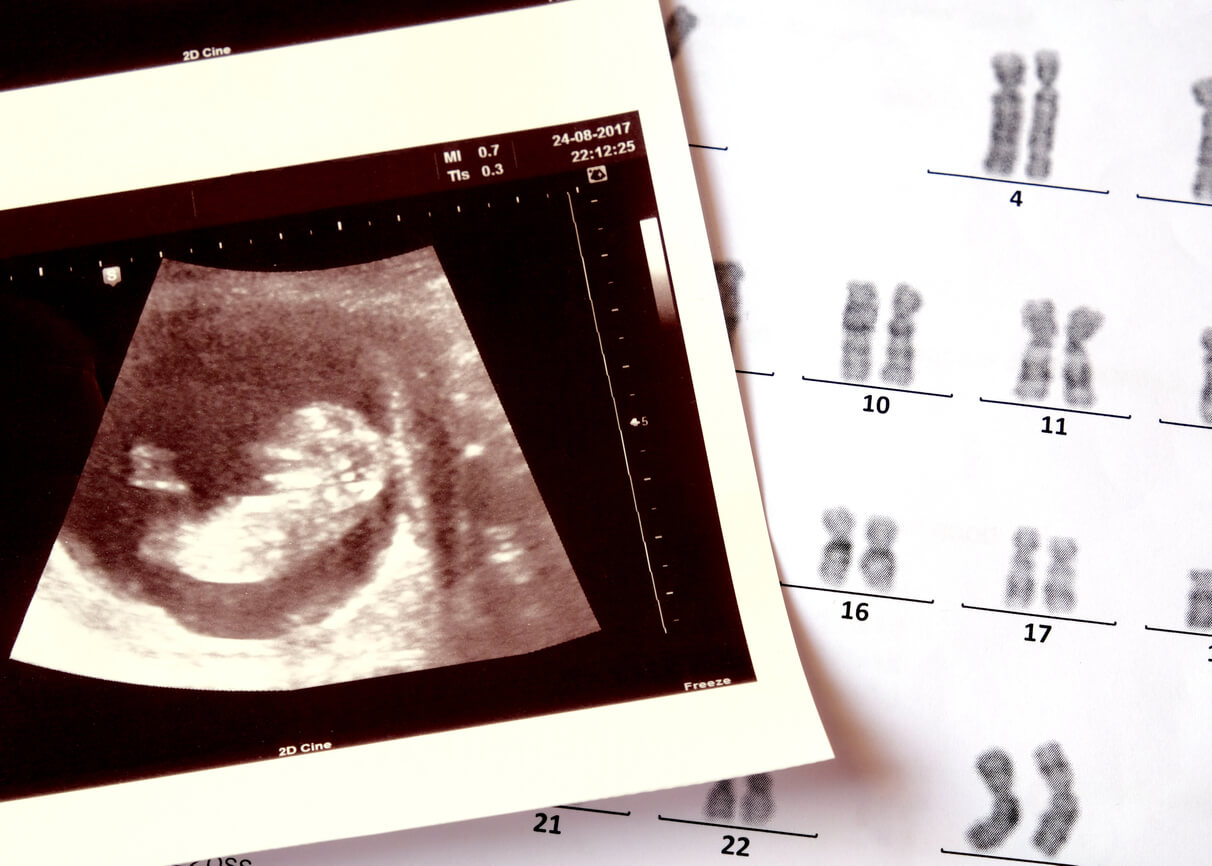

If you want to confirm the sex of your baby early in gestation, the best approach is to use the fetal DNA test. This study analyzes the genetic material of the baby that’s free in the pregnant woman’s blood and can be performed from the 10th week after conception. The main indications for fetal DNA testing include the early detection of some chromosomal diseases, such as Down syndrome, Patau’s syndrome, and Edwards’ syndrome. However, in the process of analyzing the chromosomes of the baby, the “sex pair” can be observed: XX indicates a female fetus, while XY indicates a male one.